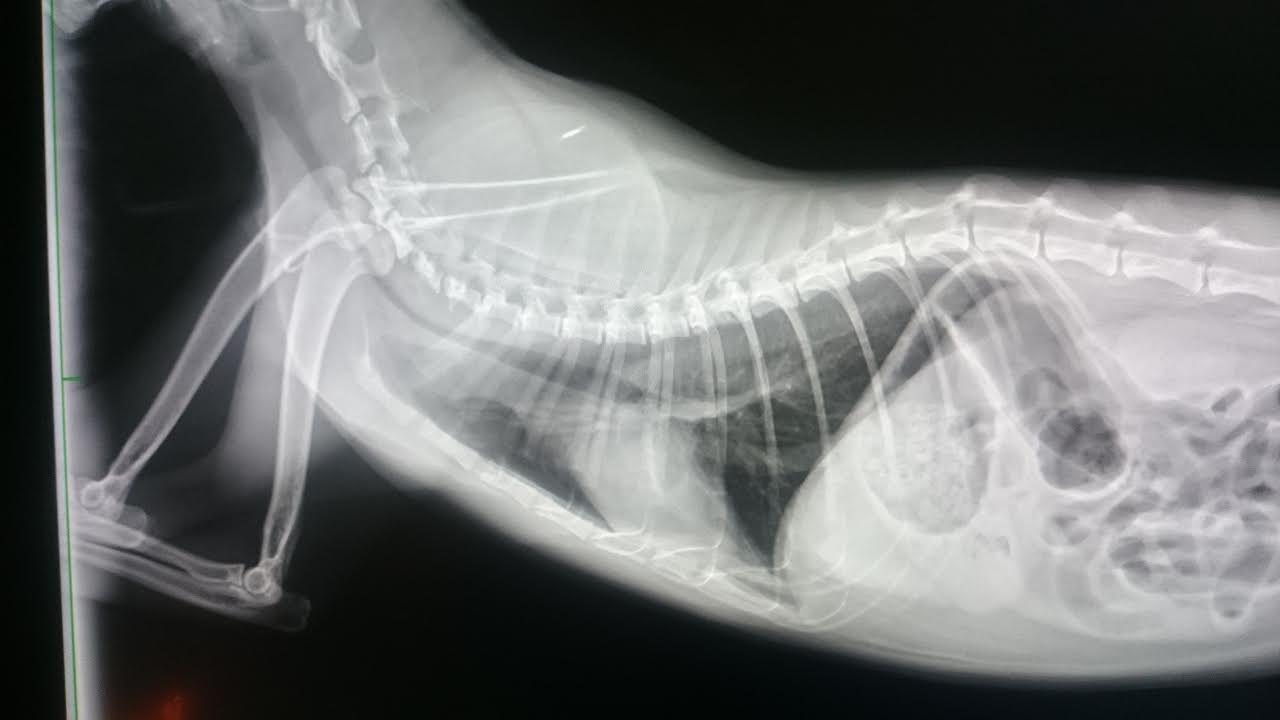

原先因喘息問題住院治療

x光顯示肺部及支氣管有浸潤(發炎)狀況

三日後(3/16)x 光也有逐漸好轉的成像

4/3當日採樣時 小斑又有些許氣喘症狀,x 光顯示肺部跟支氣管有明顯好轉

但是有氣管塌陷的狀況,可能與氣喘有關

住院期間除了做血液檢查及X光外